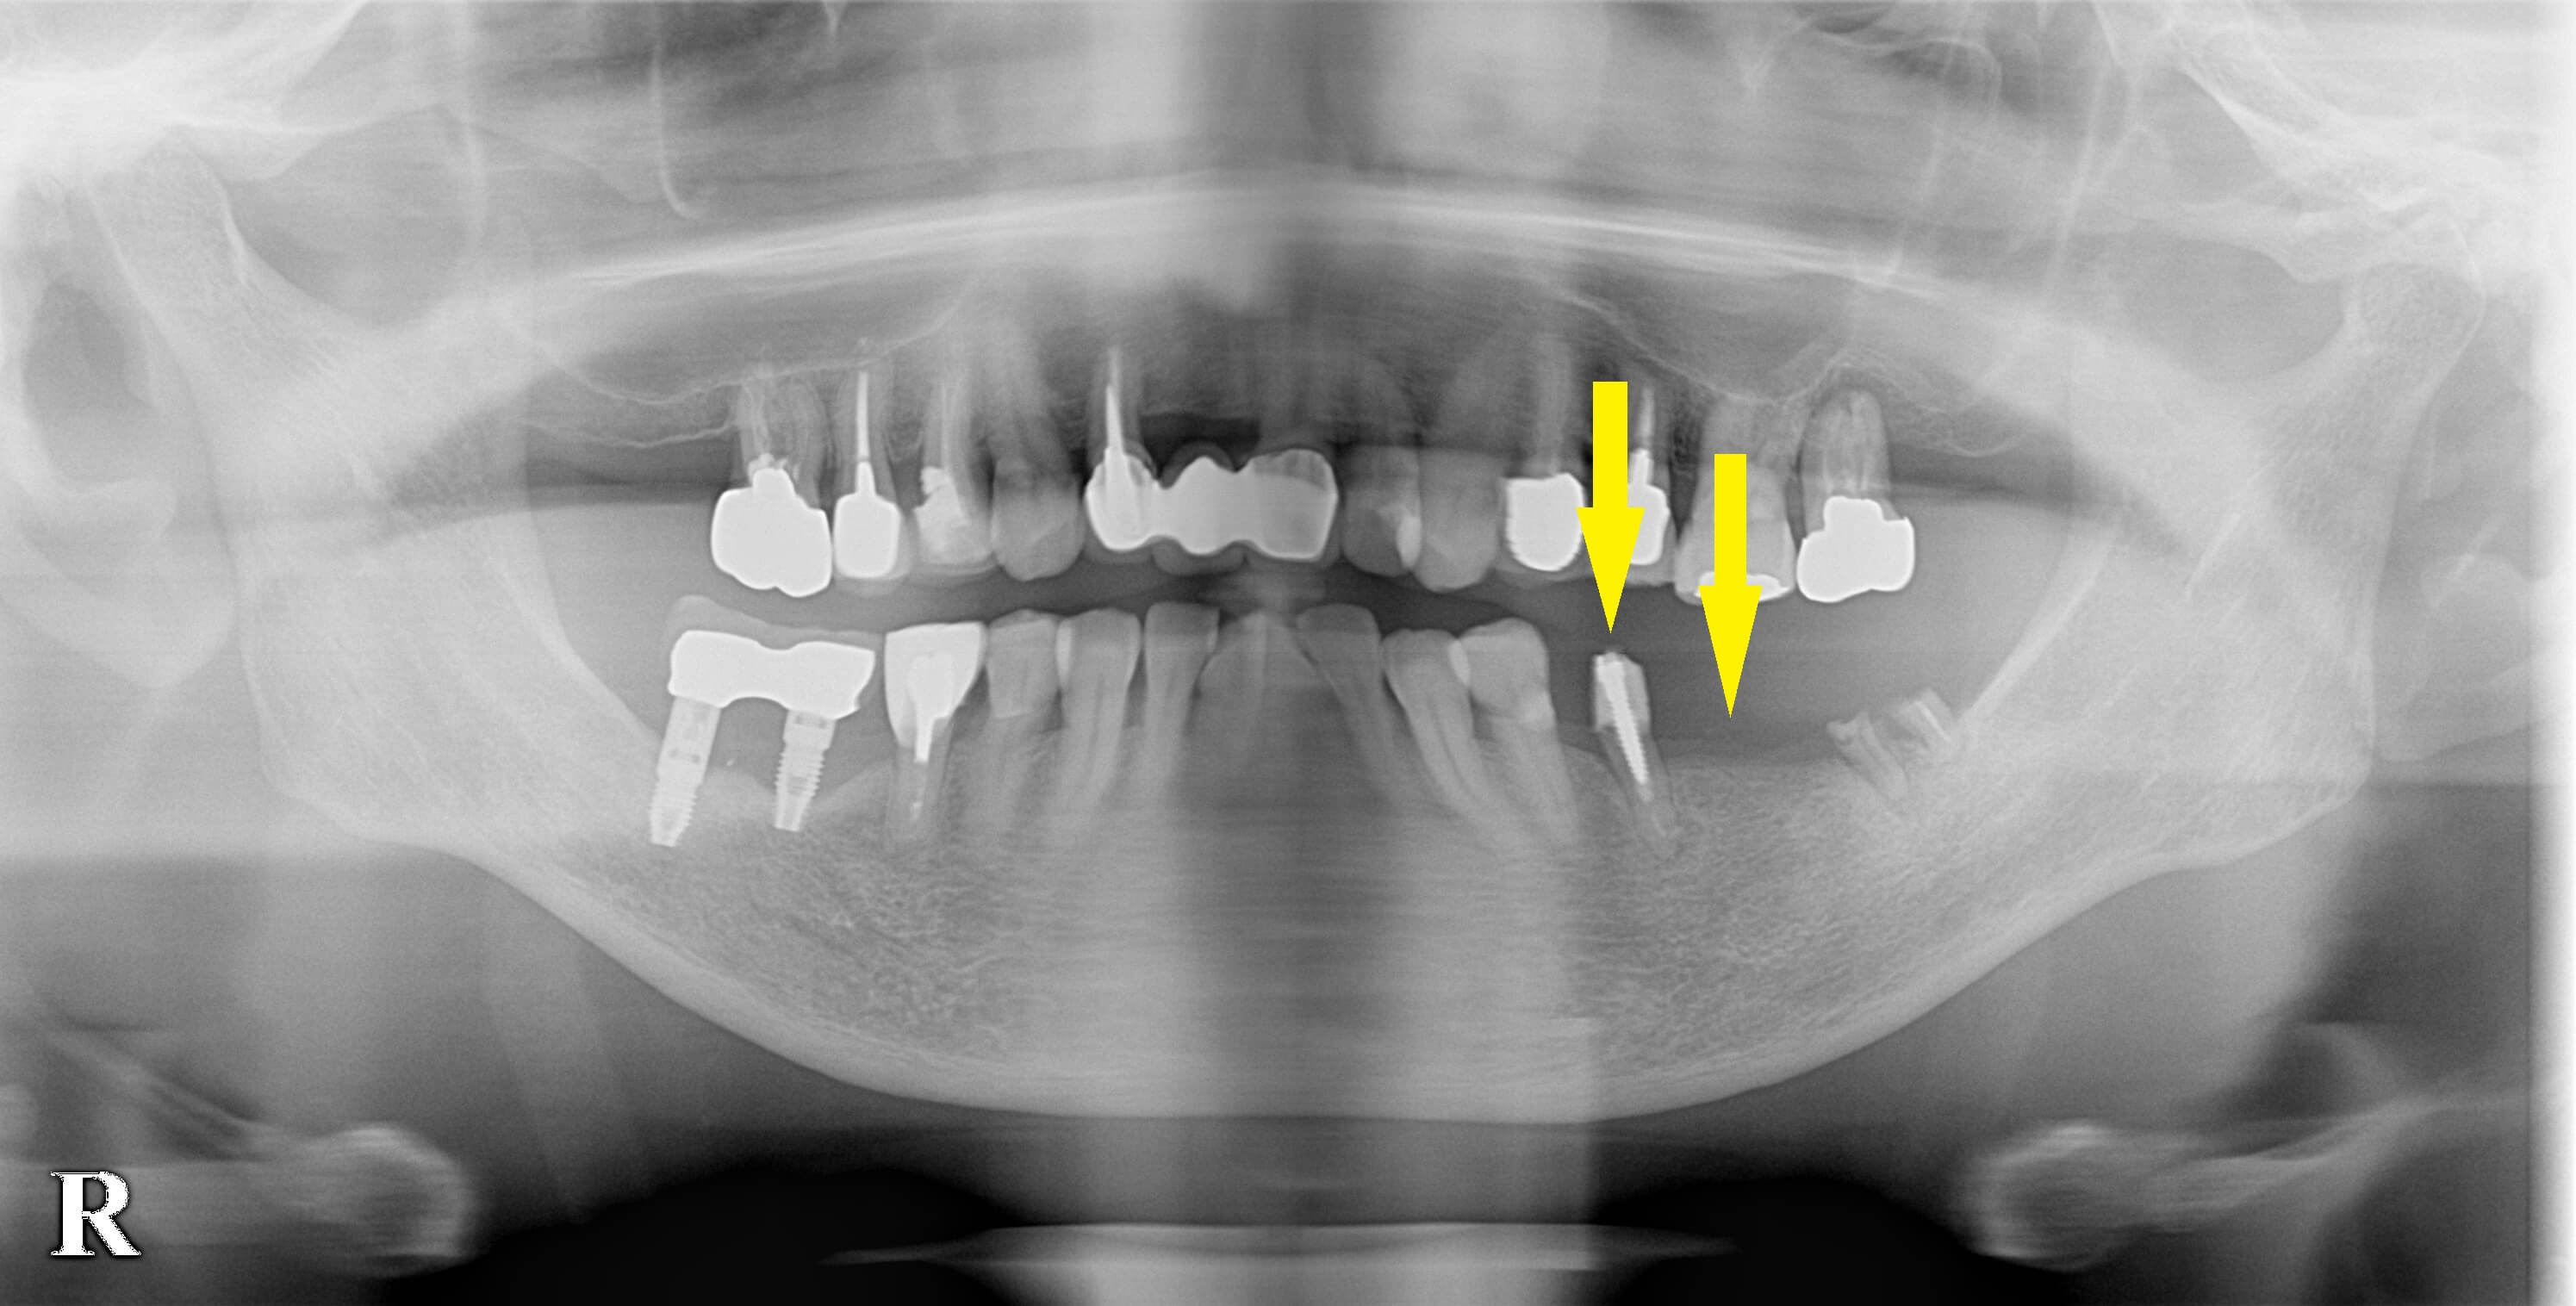

最後方の歯は、抜くだけでインプラントは埋入せず、ブリッジの支えになっていた前方の歯は、抜歯してインプラントを即時埋入、そのすぐ後方に、もう1本のインプラント埋入をするという計画を提案しました。

それで同意が得られましたので、本日2本のインプラント埋入術を施行しました。

下段の写真左が抜歯する前のCT、右が抜歯即時インプラント埋入後のCTです。

反対側の、以前治療されたインプラントは、骨が吸収されており今後再治療となる可能性が高いと、説明させていただいています。